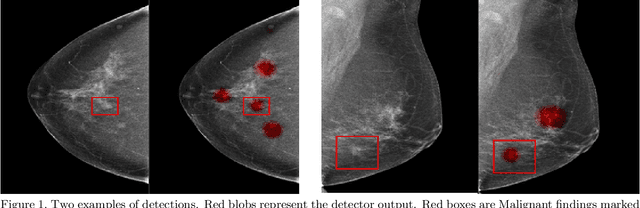

Abstract:Early detection of breast cancer through screening mammography yields a 20-35% increase in survival rate; however, there are not enough radiologists to serve the growing population of women seeking screening mammography. Although commercial computer aided detection (CADe) software has been available to radiologists for decades, it has failed to improve the interpretation of full-field digital mammography (FFDM) images due to its low sensitivity over the spectrum of findings. In this work, we leverage a large set of FFDM images with loose bounding boxes of mammographically significant findings to train a deep learning detector with extreme sensitivity. Building upon work from the Hourglass architecture, we train a model that produces segmentation-like images with high spatial resolution, with the aim of producing 2D Gaussian blobs centered on ground-truth boxes. We replace the pixel-wise $L_2$ norm with a weak-supervision loss designed to achieve high sensitivity, asymmetrically penalizing false positives and false negatives while softening the noise of the loose bounding boxes by permitting a tolerance in misaligned predictions. The resulting system achieves a sensitivity for malignant findings of 0.99 with only 4.8 false positive markers per image. When utilized in a CADe system, this model could enable a novel workflow where radiologists can focus their attention with trust on only the locations proposed by the model, expediting the interpretation process and bringing attention to potential findings that could otherwise have been missed. Due to its nearly perfect sensitivity, the proposed detector can also be used as a high-performance proposal generator in two-stage detection systems.